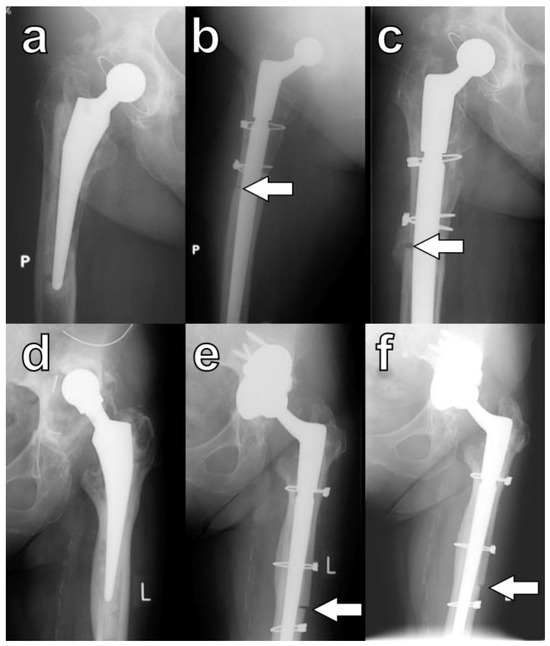

Radiographic union was defined by Abdel et al. as the presence of a callus bridging the osteotomy or the disappearance of the osteotomy line on orthogonal radiographs (Figure 4) [4].

Figure 4.

Healing of osteotomies as defined by Abdel et al. [4]: callus formation in serial radiographs of a patient K.W. taken (a) pre-op, (b) at six months, and (c) at eleven months; arrows indicate the formation of a callus at the osteotomy site. Bridging of the osteotomy site: serial radiographs of patient B.K. taken (d) pre-op, (e) at three months, and (f) at twelve months; arrows indicate direct bridging of the osteotomy site. P is an indicator for right side and L is an indicator for left side.